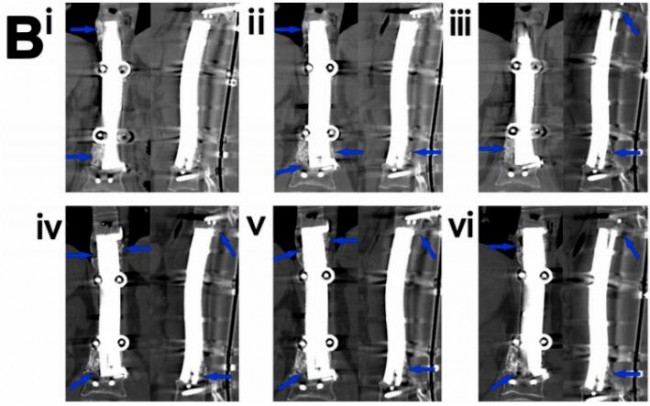

图1.3D打印多孔Ti6A14V内植物重建4 cm股骨缺损的放射学和生物力学分析。(A)植入后1个月、3个月和6个月的X线图像(i-iii)植入后1、3和6个月的计算机断层扫描图像(iv-vi)。蓝色箭头表示缺损部位或植入物外表面新形成的骨。(vii)各组的放射学评分。(n=4)(B)处死后1、3和6个月组的microCT三维重建图像(i-iii)(灰色表示钛合金,绿色表示新生骨)。(ⅳ) 各组(n=4)内植物周围和孔内区域骨体积分数的定量结果。